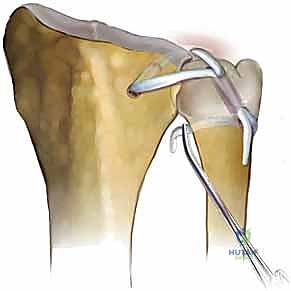

* Intra-articular Passage:

* Now, in the dorsal wound, you'll have one end of the graft exiting the radial tunnel. Take the other end of the graft.

* From dorsal, pass a straight hemostat over the ulnar head, piercing the volar DRUJ capsule just distal to the ulnar head. Use a blunt technique to avoid neurovascular injury.

* Grasp the free end of the graft with the hemostat and pull it through this capsular opening into the ulnocarpal joint space.

* Both tendon ends should now be visible through the dorsal wound: one exiting the radial tunnel, and the other having passed through the volar capsule.

* Passing Graft through Ulna:

* Using a suture retriever or a curved hemostat, pass both tendon ends through the ulnar bone tunnel, starting from the fovea and exiting at the ulnar neck.

* Wrapping the Graft:

* This is the final anatomical configuration. A curved hemostat is used to guide the two tendon ends around a portion of the ulnar neck in opposite directions.

* One limb of the graft should pass deep to the ECU sheath, reconstructing the dorsal radioulnar ligament.

* The other limb should pass around the volar neck of the ulna, reconstructing the volar radioulnar ligament.